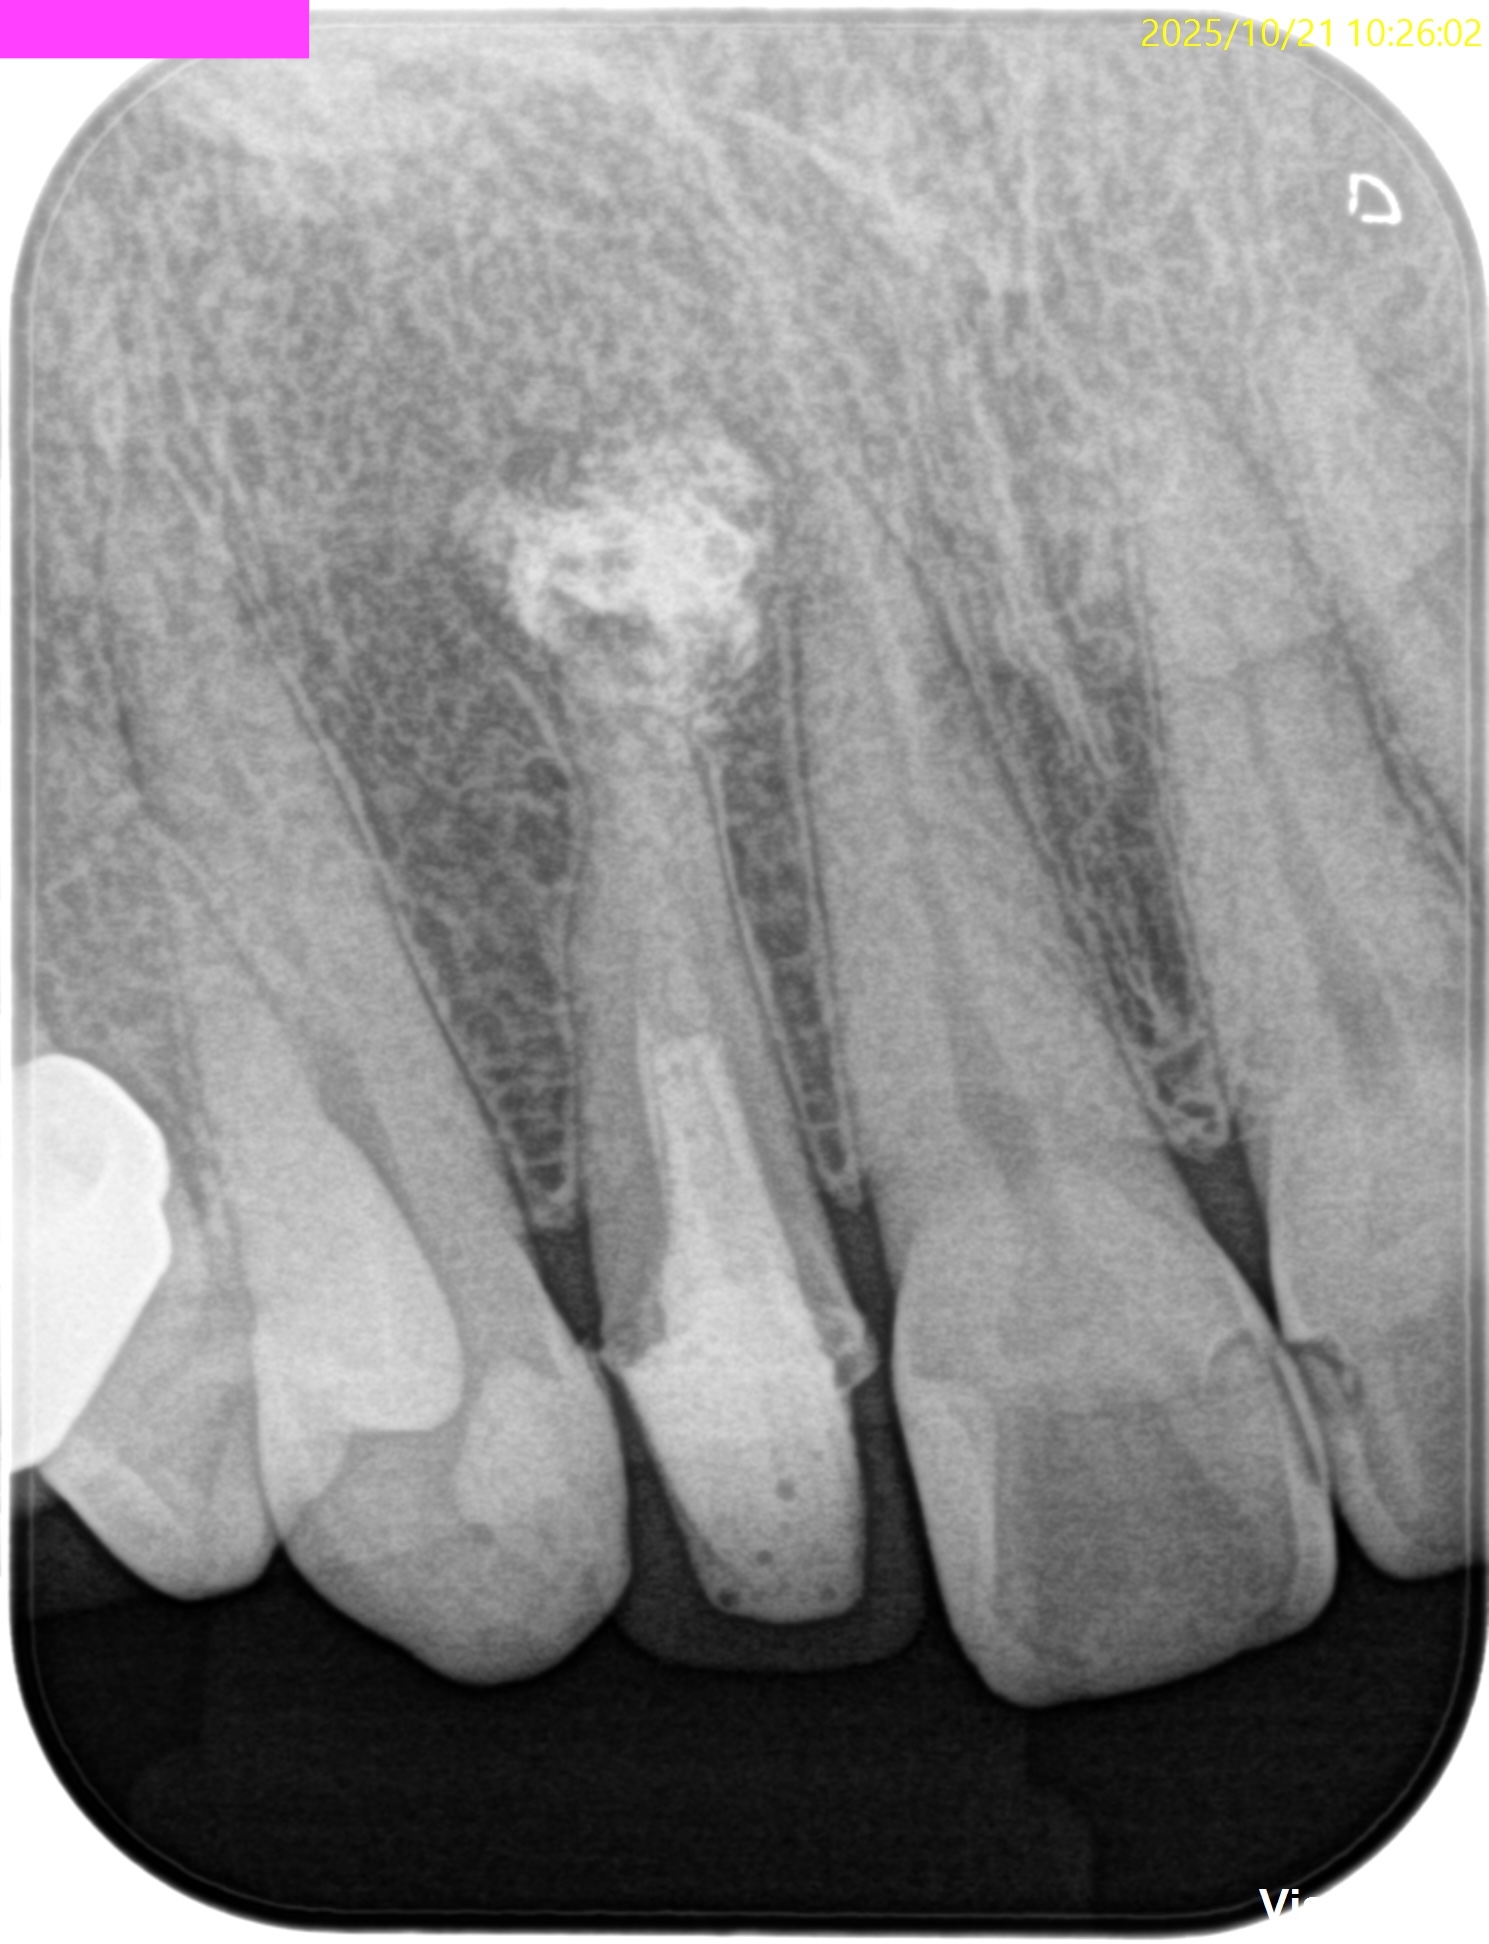

PA(2025.10.21)

何かが根尖から突き出ている。

これが違和感の原因か?と言えば、

違和感の原因はこれではなく、根管の細菌であろう。

もうすでに大きく形成して大きく根充されている以上、再根管治療に勝ち目はない。

そう。Apicoectomyである。